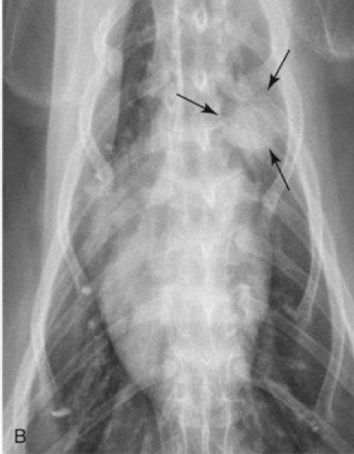

What is the likely condition? What are the arrows pointing to?

Aspiration pneumonia (bc right middle)

red: air bronchogram

blue: border effacement

yellow: lobar sign